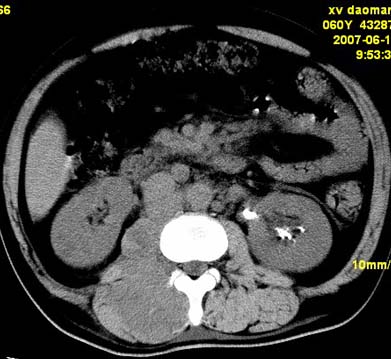

以下是引用还珠格格在2007-6-26 15:05:00的发言:[br]右侧腰大肌、同侧竖脊肌明显肿胀,呈不均匀密度减低影,右肾受压右上前移,脂肪间隙部分消失,另左侧肾盂内可见高密度影,是结石还是造影剂? 不知道病人用造影剂没有?考虑 右侧腰大肌及右侧竖脊肌寒性脓肿形成。[br][br][本贴已被 还珠格格 于 2007-6-26 15:21:35 修改过]

以下是引用小初学者在2007-6-26 15:42:00的发言:[br]1\\右侧腰大肌、同侧竖脊肌脓肿[br]2\\左侧肾盂结石

以下是引用刘明在2007-6-26 16:00:00的发言:[br][br]右侧竖直肌及腰大肌肿胀,脂肪间隙难辨,腹膜后血管旁见多个肿大淋巴结影,椎体附件右侧有压迫吸收、未见硬化迹象,考虑椎旁冷脓肿可能[br]左侧肾盂内可见高密度影,周围有毛刺,本图象是平扫,不是增强,应该是结石[br]

以下是引用hhcckk在2007-6-27 9:41:00的发言:[br]肾周筋膜增厚,胰腺影肥大,楼主是考我们了,我考虑是胰腺炎引起的腰部感染,形成的蓝棕色斑,也称gray-turner征,另外腹膜后怎么这么多的淋巴结,转移也要考虑[br]结核三个月没有骨破坏?寒性脓肿累及到竖脊肌的少见,所以我考虑结核的可能性不太大[br]左肾内高密度影,密度不太均匀,左肾有积水的表现,考虑是结石[br]期待楼主老师的结果